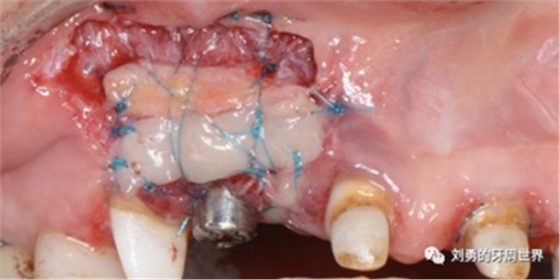

該方式齦瓣固定的效果差,術后血供差,為了改善血供,我們提倡下面的改良縫合方式,血供更好,成功率更高,如下圖:

通過用縫線壓迫的方式固定,術后愈合的過程齦瓣始終與受區(qū)骨膜貼合,而不會移動。

但是該方法對于縫合技術要求較高,因此本人嘗試了新的方法,膜釘固定:

該方法操作簡單,但是需要擇期局麻下拆除膜釘。